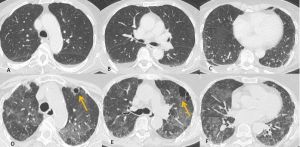

Figura 1: Uomo di 75 anni con infezione da SARS-CoV-2. Le immagini TC assiali (A-B-C-D) e ricostruzioni MPR sul piano sagittale (E) e coronale (F) mostrano la tipica presentazione della polmonite da COVID-19 caratterizzata dalla presenza di aree di aumentata densità con aspetto a “vetro smerigliato” cui si associa ispessimento liscio dei setti interlobulari che mostrano prevalente distribuzione subpleurica. La localizzazione delle aree di iperdensità in sede subpleurica è caratteristica di questa infezione come evidenziato particolarmente nell’immagine A in cui le aree a “vetro smerigliato” si dispongono lungo la scissura del lobo accessorio dell’azygos e nell’immagine E in cui è evidente la distribuzione delle alterazioni lungo le scissure.

In TCAR si caratterizza per la presenza di aree a “vetro smerigliato” diffuse in entrambi i polmoni come la maggior parte delle polmoniti virali descritte di seguito, queste aree tuttavia si contraddistinguono per la prevalente distribuzione subpleurica e per la presenza nel contesto di ispessimento liscio dei setti interlobulari (Figura 1). Versamento pleurico e linfadenopatie sono reperti più rari.

È importante sottolineare che nei casi gravi in cui le aree di aumentata densità tendono a confluire coinvolgendo tutto il parenchima polmonare, la diagnosi differenziale con altre patologie non è semplice senza un adeguato supporto clinico-laboratoristico.